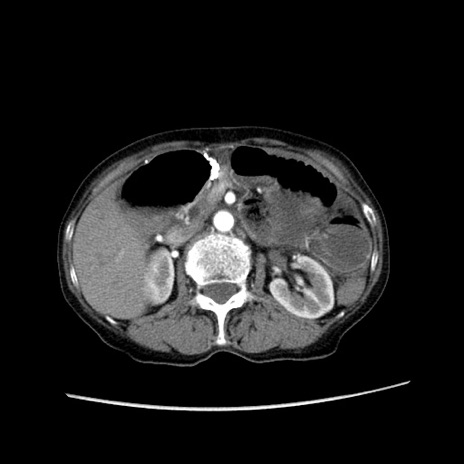

症例25(横断像)

【症例】80歳代女性

【主訴】胸のつかえ感

【現病歴】約9時間前に食後から胸のつかえた感じあり、嘔吐あり、来院。

【既往歴】胃癌(全摘)、胆摘、虫垂炎

【身体所見】心窩部に圧痛あり、反跳痛なし。

【データ】WBC 5700、CRP 0.05